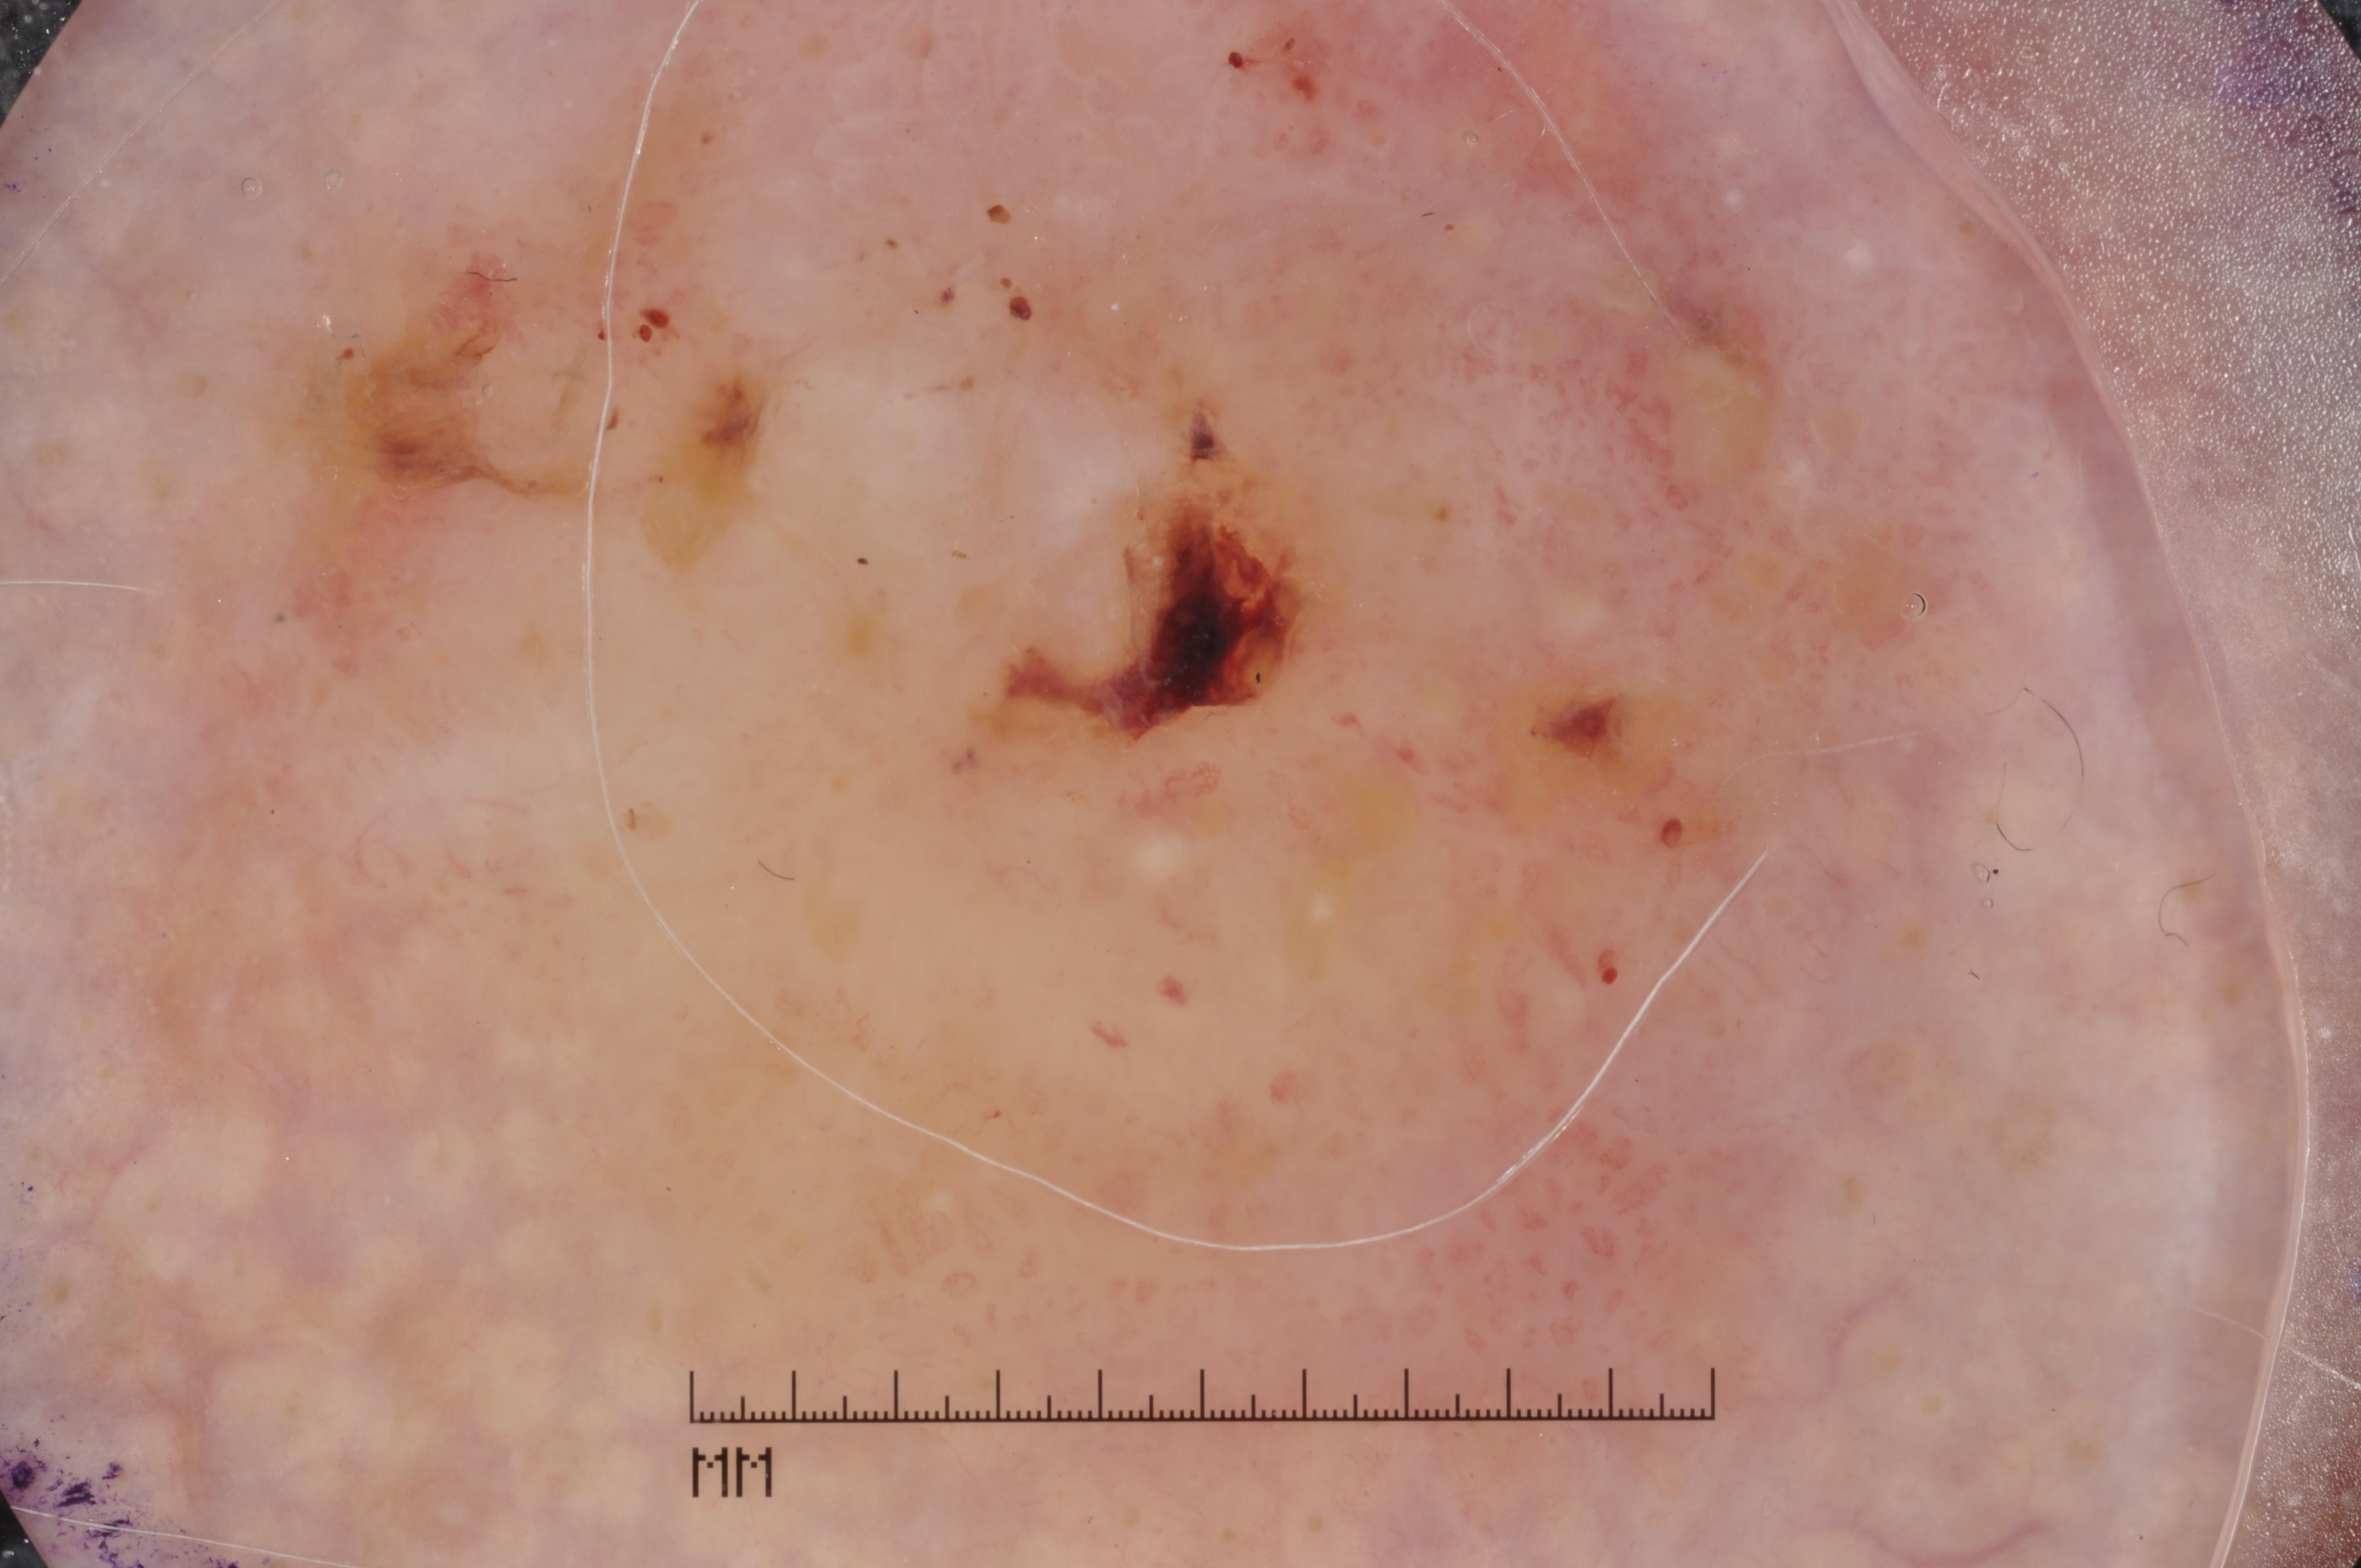

{

"age_approx": 60,

"anatom_site_general": "posterior torso",

"concomitant_biopsy": true,

"dermoscopic_type": "contact non-polarized",

"diagnosis_1": "Malignant",

"diagnosis_2": "Malignant melanocytic proliferations (Melanoma)",

"diagnosis_3": "Melanoma Invasive",

"diagnosis_confirm_type": "histopathology",

"image_type": "dermoscopic",

"lesion_id": "IL_1206610",

"melanocytic": true,

"sex": "female"

}